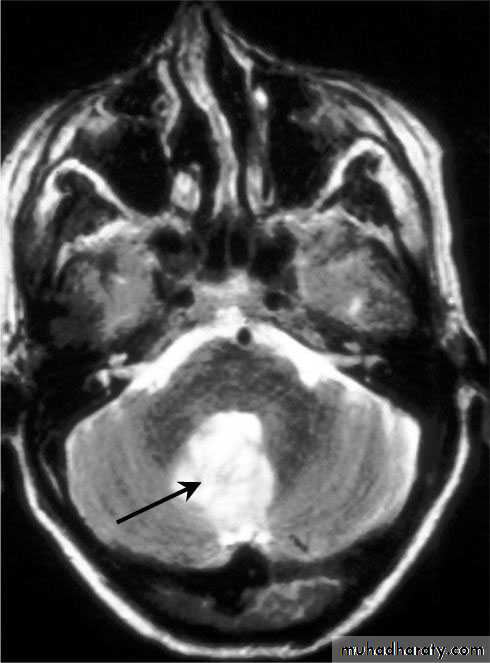

Brain Abscess MRI

د.عبدالرحمن

• CT or MRI is the investigation of choice.

• They will show a single (or multiple) space occupying lesion that is well delineated with an enhancing wall, with variable surrounding oedema.